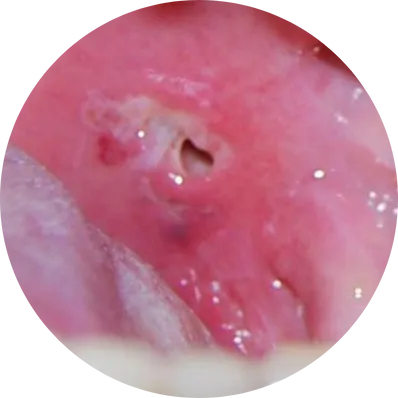

Types of Tonsillectomy

This is the traditional method where the surgeon removes the tonsils using surgical instruments without heat. It is effective, but may cause more postoperative pain and minor bleeding compared to newer techniques.

Uses electric current to cut tissue and control bleeding simultaneously. This reduces intraoperative bleeding but may cause slightly more pain later due to heat exposure.

A modern technique that uses controlled radiofrequency energy combined with saline to dissolve tonsil tissue at low temperatures. Benefits include minimal pain, less bleeding, and faster recovery. Ideal for children and adults.

Uses ultrasonic energy to cut and coagulate tissue. Results in less bleeding, minimal tissue damage, and smoother healing.

A powered instrument shaves the tonsil tissue layer-by-layer instead of cutting it out entirely. Especially useful for partial tonsil reduction (tonsillotomy).

Uses a focused laser beam to vaporize tonsil tissue. Suitable for selected cases and may be used for partial or complete removal. Offers less bleeding but may cause temporary throat discomfort.